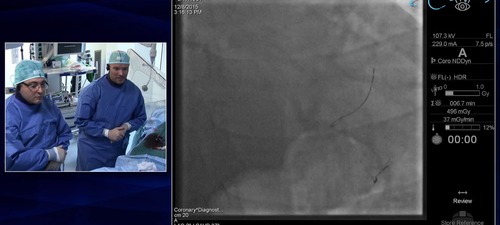

FFR measurement is performed using the Navvus pressure micro catheter.  Dr. Nicolas M. Van Mieghem shows how to troubleshoot variability in FFR measurement to get a stable FFR and useable FFR measurement.

This case is to inform and educate interventional cardiologists on:

• Strategy selection to approach significant true bifurcation lesions

• Implementation of FFR assessment in bifurcation lesions

• Implementation of FFR in side-branch assessment after provisional stenting

• Use of microcatheter based FFR technology